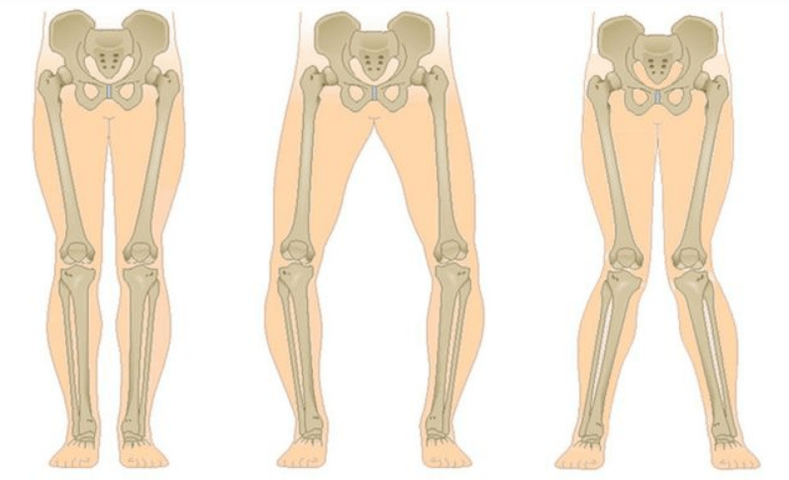

The last stage of gonarthrosis is characterized by the fact that the pain becomes almost constant, causing anxiety not only while walking, but also at rest, and even at night, when patients have to find a comfortable position to sleep.Movement is more limited: it is difficult to fully bend and straighten the leg.The joint deforms and increases in volume.Valgus (X-shaped) or varus (O-shaped) leg deformities are often observed.The gait becomes unstable and he stumbles.In severe cases, a cane or crutches are needed.

Depending on the number of affected joints, unilateral and bilateral gonarthrosis are distinguished.